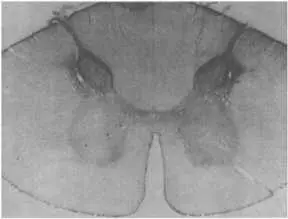

Это повышение реактивности наряду с длительностью разряда после прекращения стимуляции навело некоторых исследователей на мысль, что здесь действует какой-то нейромедиатор, который высвобождается и инактивируется довольно медленно. И действительно, был выделен нейропептид, названный веществом Р , — медиатор, содержащийся в нейронах задних рогов спинного мозга (на рис. 113 показана локализация этого вещества на срезе спинного мозга обезьяны). Это, по-видимому, специализированный медиатор, передающий сигналы от периферических болевых рецепторов в центральные отделы нервной системы. Поскольку вещество Р оказалось широко распространенным и в нейронах головного мозга, его функции, вероятно, не сводятся к передаче одних только болевых импульсов.

Рис. 113. Вещество Р в задних рогах спинного мозга обезьяны.